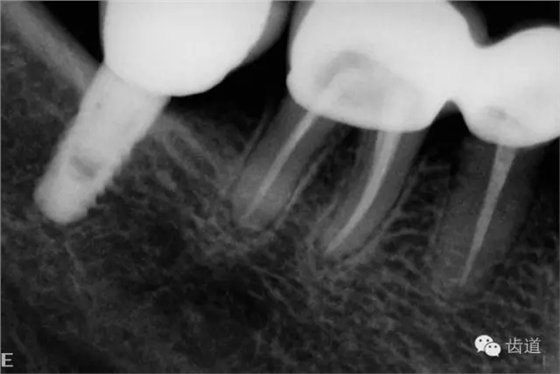

2、45,46術(shù)前片顯示根管上段充填物,根管影像不清晰,少許根尖暗影

3、34術(shù)前片顯示遠中面暗影近髓